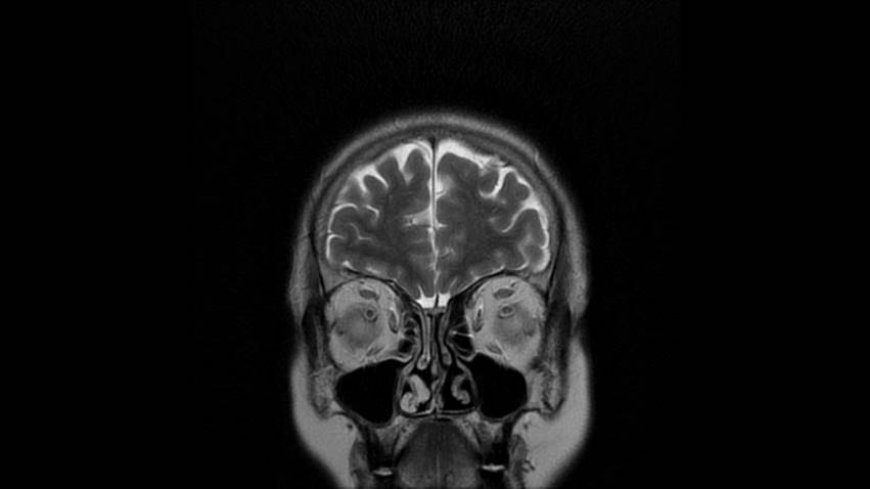

MRI of Brain

Coronal T2